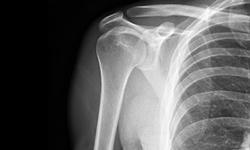

Teaching with the media is brain friendly because it provides interactive abstract learning that utilizes the categorical memory and requires little intrinsic motivation. Neuroanatomy is an integral part of human anatomy that is taught to medical students. This preparation is an attempt to offer interactive learning of the practical demonstration of peripheral nerve injuries to medical students and prospective physiotherapies who are studying for higher degree in neuroanatomy. It is focused on the anatomy of brachial plexus and the clinicoanatomic features of upper trunk injury using annotated photograph of a young man with traumatic Erb’s palsy.

A Case of Erb's Palsy (Erb-Duchenne Palsy) in an Adult |